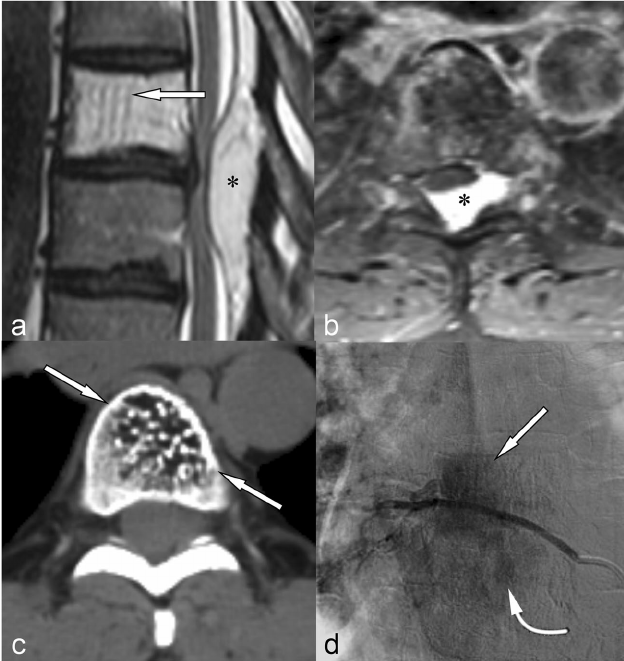

The spine is a frequent site affected by tumors and cancers both arising in the spine and those spreading from other sites in the body. The tumors that commonly affect the spine are Osteoid osteoma, Osteoblastoma, Aneurysmal Bone Cyst, Giant cell tumor, Eosinophilic granuloma, lymphoma and Plasmacytoma. The cancers that commonly affect the spine primarily are Multiple Myeloma, Leukemia, Ewing’s Sarcoma, Osteosarcoma and Chondrosarcoma.

The cancers that spread to the spine (metastasis) from other sites in the body are prostrate cancer, breast cancer, lung cancer, thyroid cancer and renal cancer. Of these, prostrate cancer and breast cancer metastasis are bone forming (osteoblastic or osteosclerotic) whereas the other cancers are bone destroying (osteolytic).

Frequently, surgery is preceded by a CT guided embolization (of blood vessels supplying the tumor) to decrease blood loss during surgery. The spine surgery in these cases involves decompression of nerves, removal of tumor, sending material for biopsy, reconstructing the defect left behind after removing the tumor and fixing the spine with screws and rods made up of titanium.